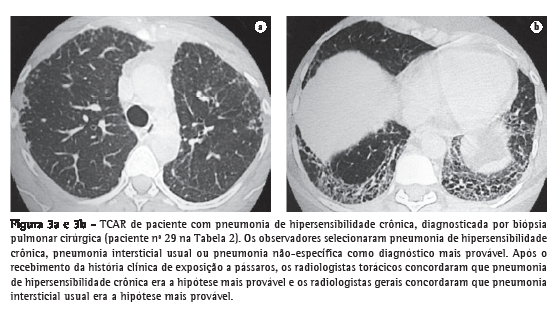

Os dois radiologistas torácicos concordaram quanto ao diagnóstico mais provável para cada paciente em 48,3% (κ = 0,42) e 62,1% (κ = 0,58) dos casos, respectivamente, antes e após o recebimento das informações clínicas. Os dois radiologistas gerais concordaram quanto ao diagnóstico mais provável para cada paciente em 37,9% (κ = 0,32) e 36,2% (κ = 0,30) dos casos, respectivamente, antes e após o recebimento das informações clínicas (Figuras 1-3).

Nosso estudo teve algumas limitações. Embora as DPIs sejam relativamente incomuns, o número de casos analisados foi menor que o investigado em outras séries. Estudos futuros devem investigar amostras maiores para a obtenção de conclusões mais significantes. Outra limitação foi o fato de os pacientes terem sido selecionados em um ambulatório altamente especializado de um centro terciário, o que pode ter levado à inclusão de indivíduos com DPIs complexas, afetando a concordância entre observadores. O ambulatório é também um centro de referência para algumas afecções, inclusive pneumonite de hipersensibilidade (PH). Isso explica a distribuição não usual dos casos, sendo que a PH foi uma das doenças mais comuns, e a fibrose pulmonar idiopática foi menos frequente que em outras séries. No entanto, os pacientes incluídos constituíram uma amostra representativa das doenças observadas em nossa população.